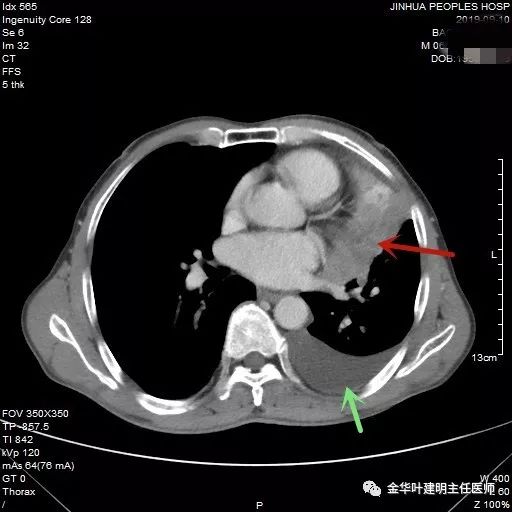

红色箭头示不张的肺,绿色示胸水

肿瘤与左肺动脉主干关系密切

黄色箭头示左肺下叶支气管外壁受累,没有间隙

黄色区域示左下叶支气管受压,与肿瘤间没有间隙

肿瘤巨大,并与心脏关系密切,提示可能需切开心包处理